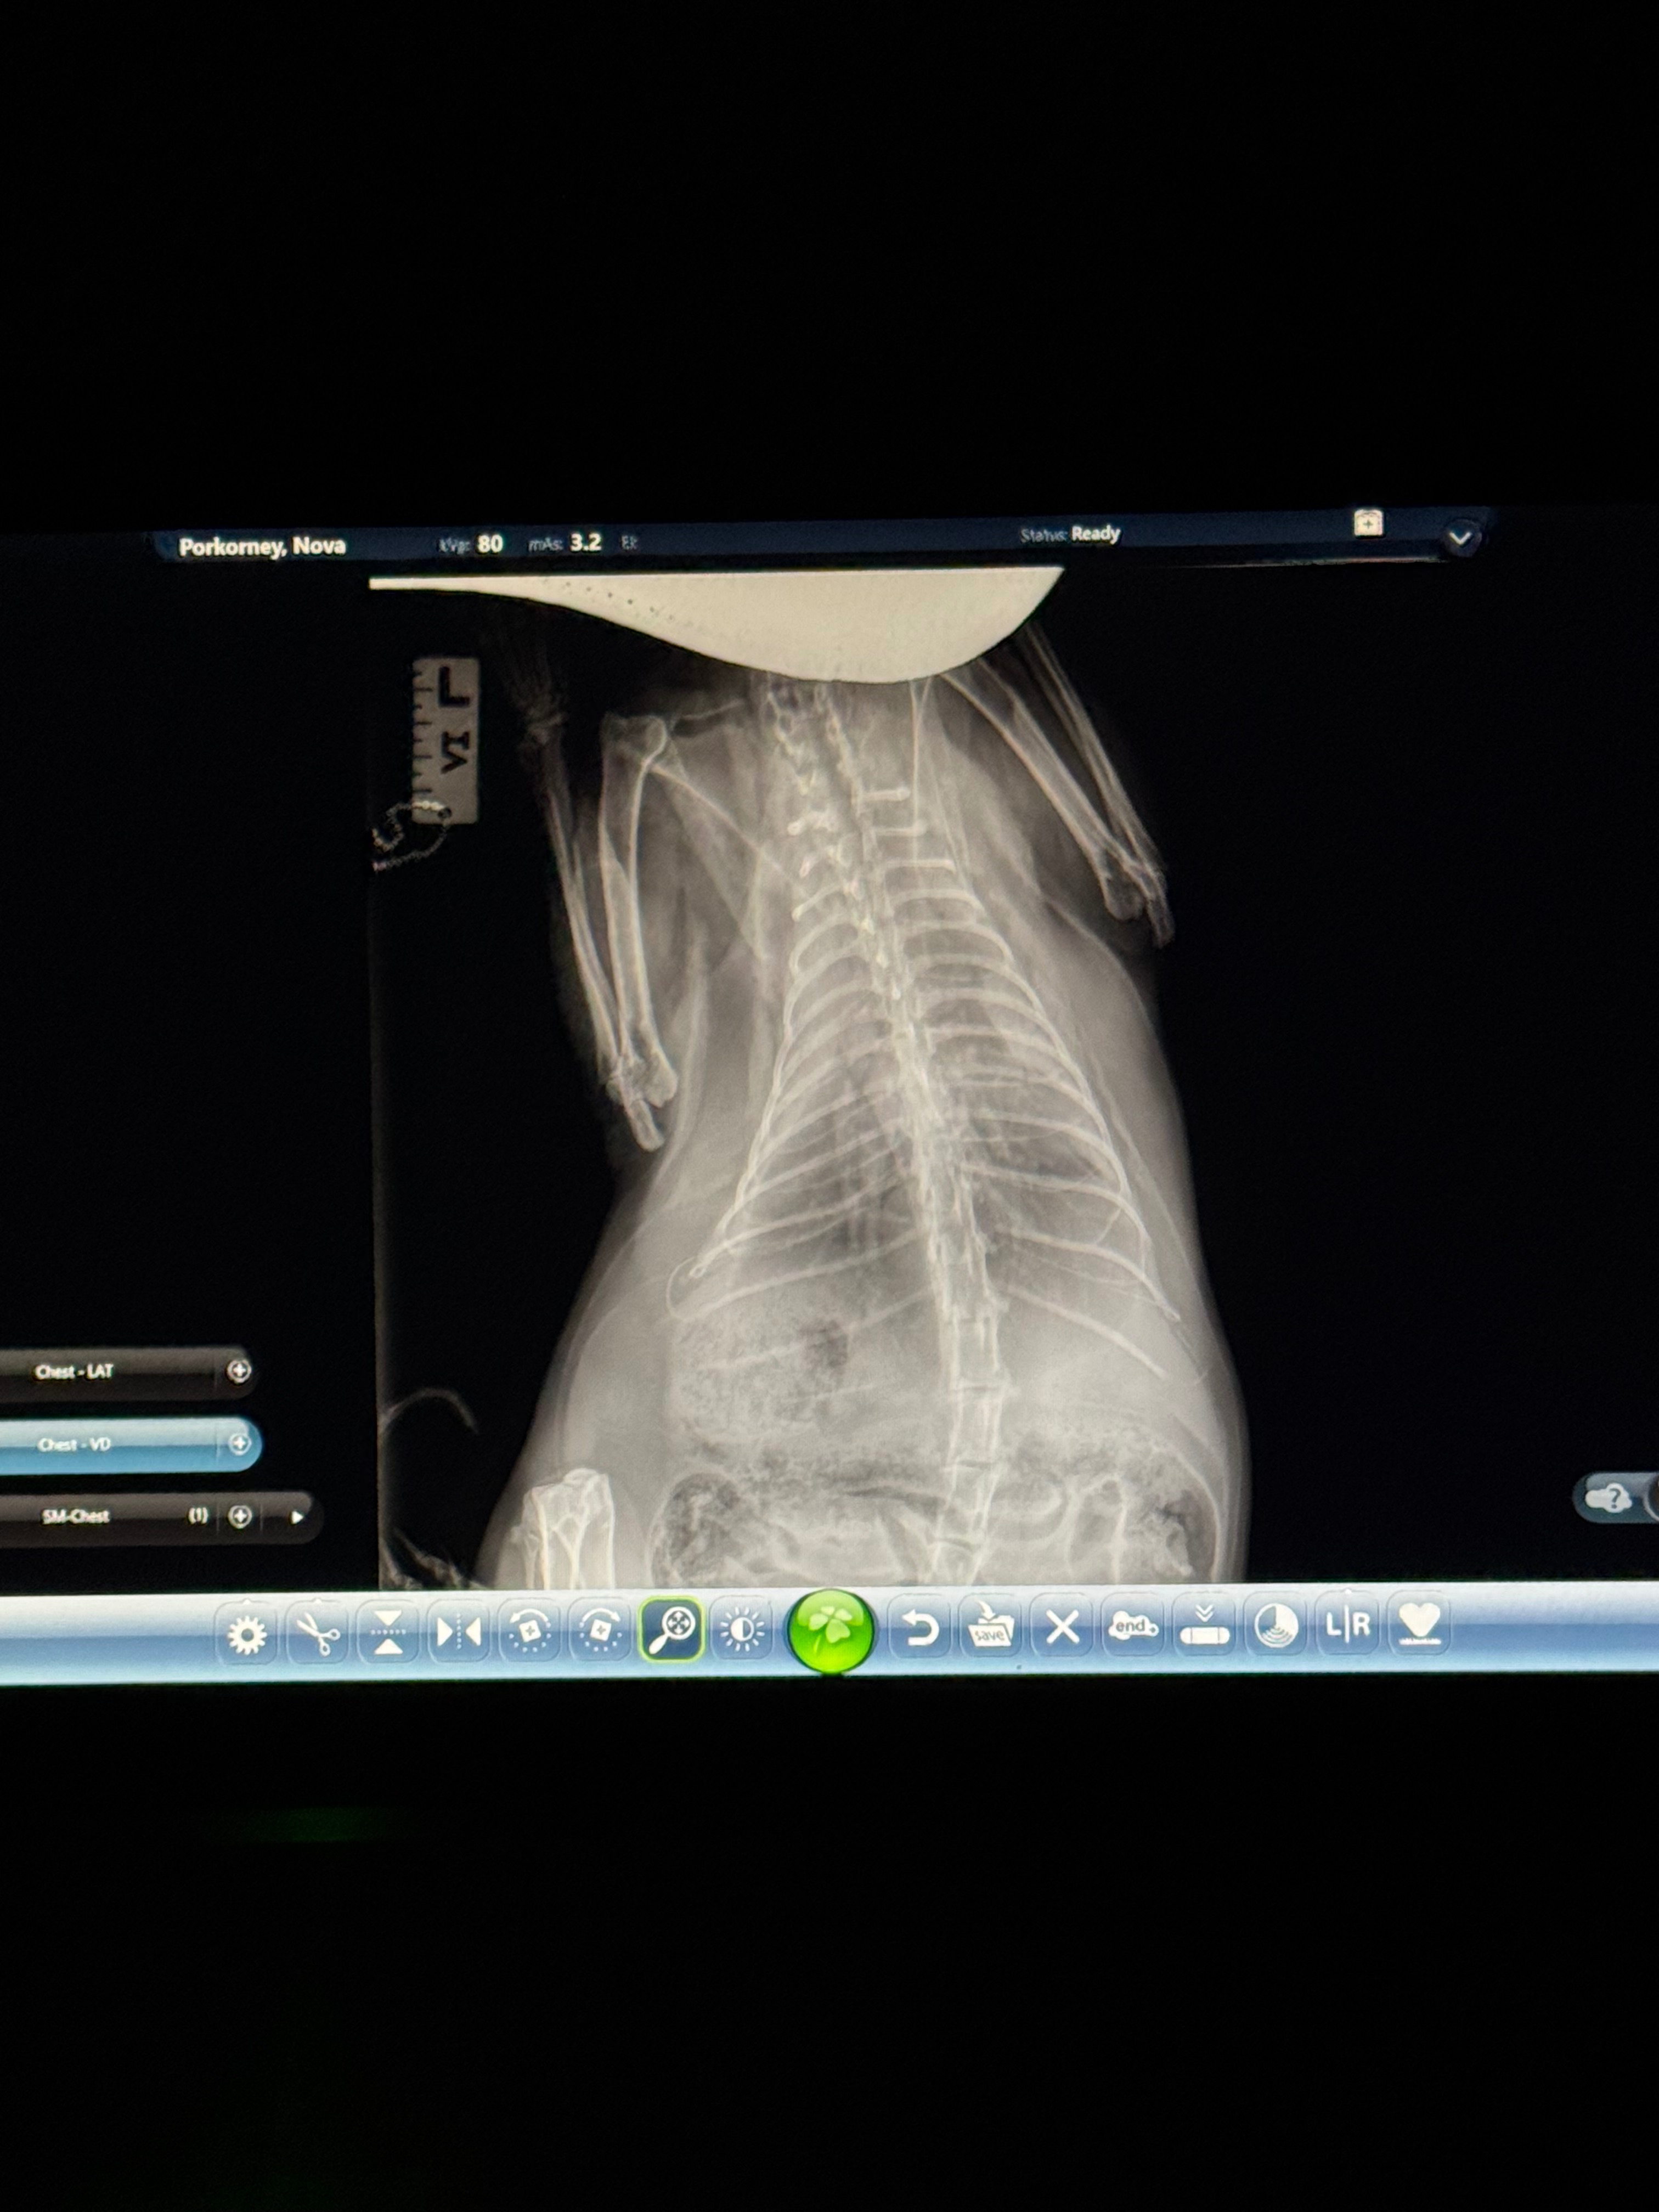

Hi. Some of you may know I found out around Christmas time that my kitty Nova was unfortunately diagnosed with diabetes. First, we went from seeing the vet weekly to get his insulin regulated, then to every other week. He began to get slightly better, until this last week I realized his breathing was very short and sharp. Going into our next follow-up appointment, I got x-rays and seemingly, there's fluid surrounding the inside and outside of my poor kitty's lungs. The fluid is causing so much pressure on his heart and lungs, his left lung has already begun to partially collapse, making it extremely difficult for him to breathe and for his heart to beat.